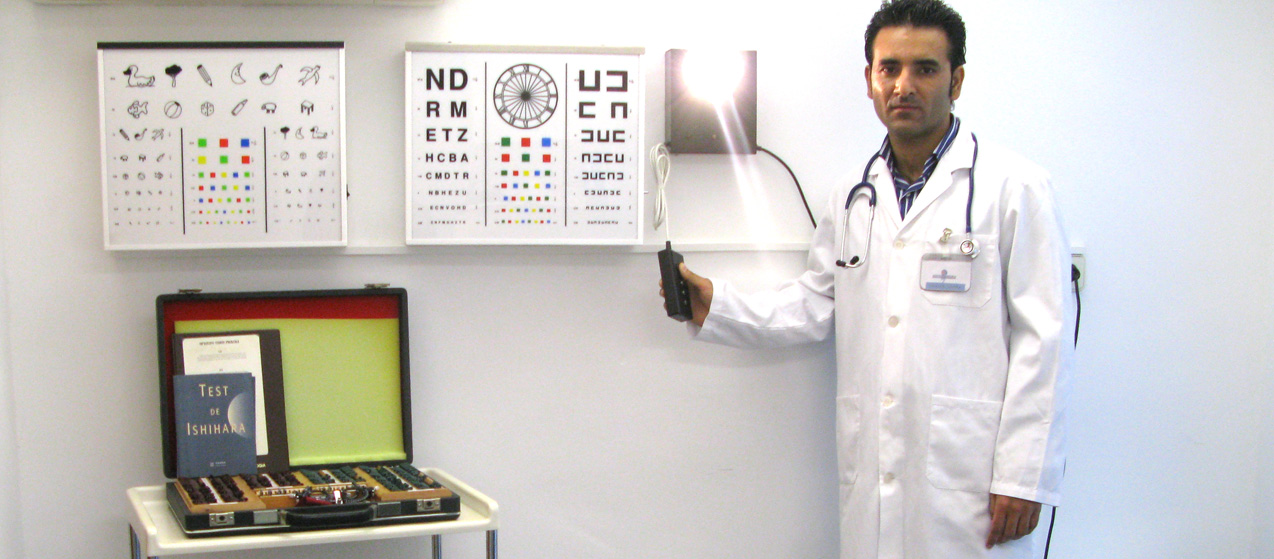

Avaliação Clínica para Atestados (Doença, Robustez, Caçador, Pesca,Frequência Escolar, Primeiro Emprego; Uso e porte de Arma, Saúde Oral, etc)

A emissão de um Atestado Médico é um ato clínico subsequente a uma avaliação clínica (História Clínica e Exame Objetivo e eventual pedido de Exames de Diagnóstico). A Consulta Clínica para a emissão destes Atestados Necessita de marcação prévia.